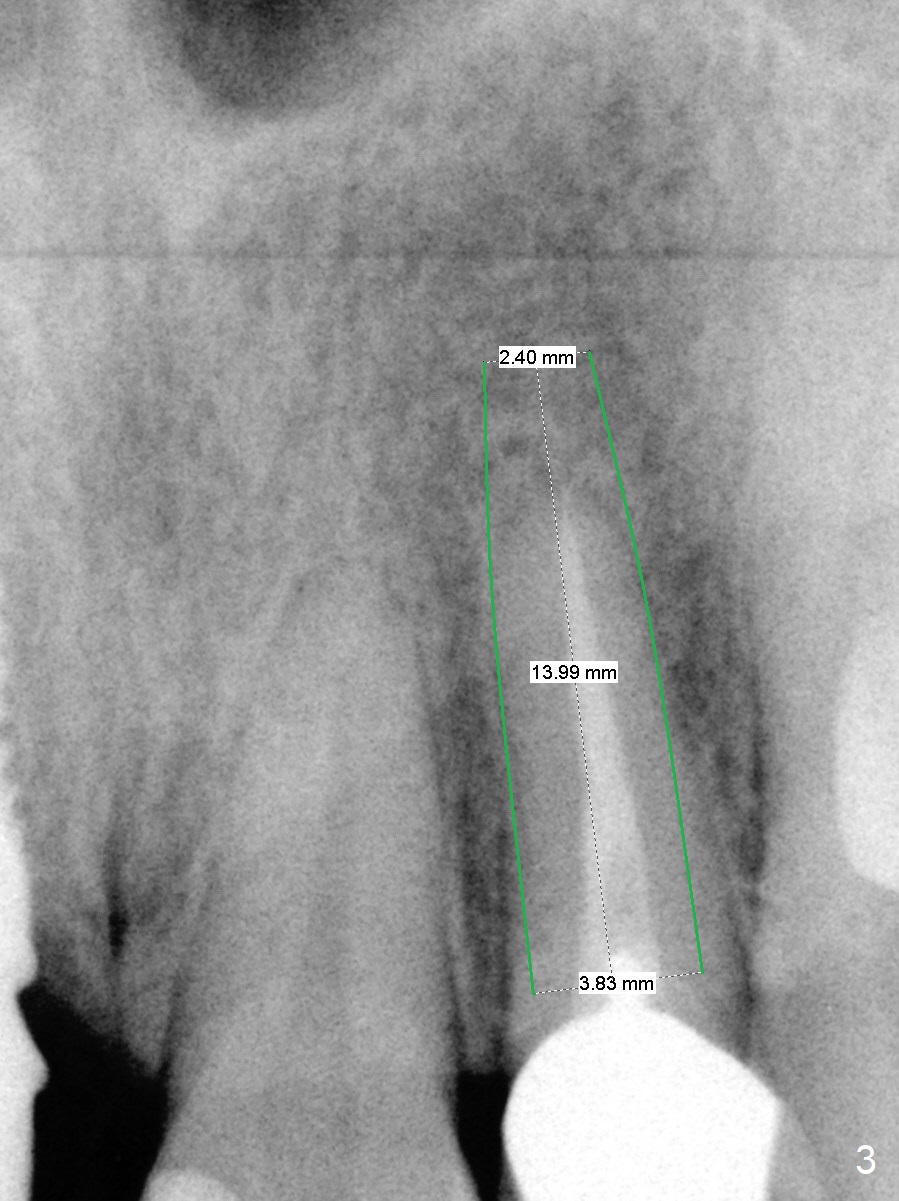

Narrow Mesiodistal Space

A 37-year-old woman needs an implant at #10 because of crown recementation twice (Fig.1). The smallest 2-piece implant, 3.8 mm, appears to be larger than the root. The implant may perforate the buccal apical concavity (Fig.2 arrowheads). Measure the extracted root. If it is wider than 3.8 mm mesiodistally, place the 2-piece implant. Otherwise use a 3 mm 1-piece one. Do not forget the angled one. Retrospectively, the 3.8 mm implant is large for the site. A 3.0 or 2.5 mm one is more appropriate (Fig.2).